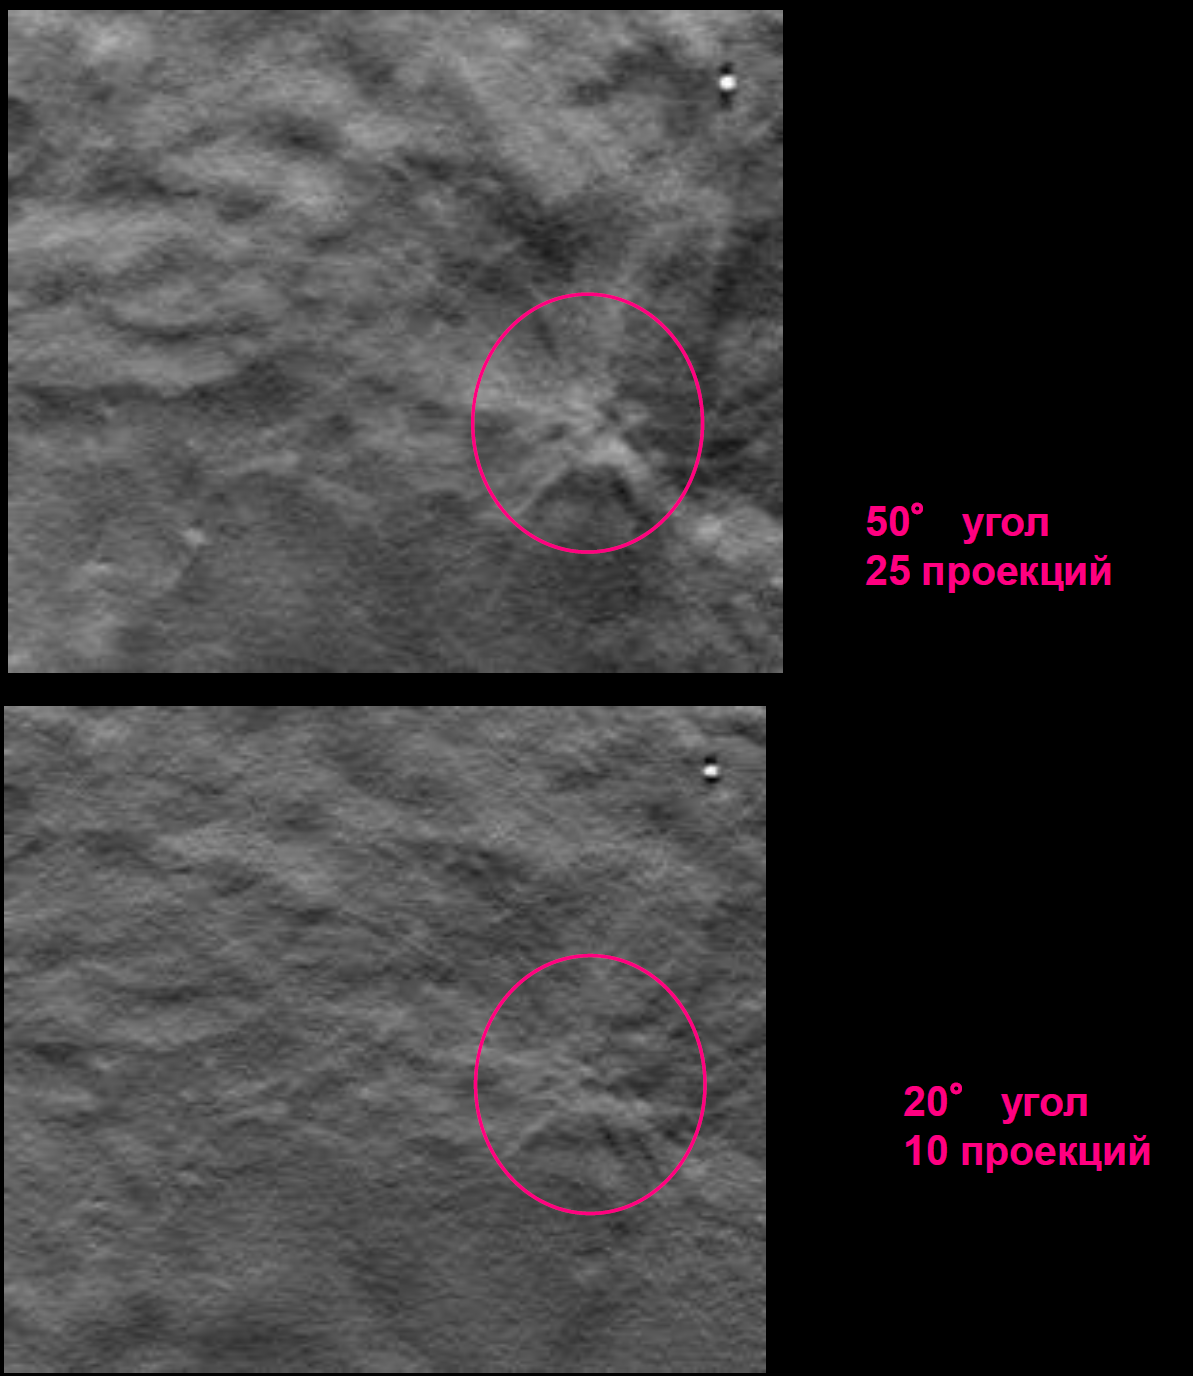

Факторы качества цифрового томосинтеза (DBT)

- Угол наклона рентгеновского излучателя. Больший угол даёт больше информации, т.к. уменьшается степень наслоения соседних объектов.

- Количество получаемых проекций. Чем больше количество проекций, тем меньше уровень артефактов.

- Толщина среза влияет на степень наслоения по вертикали соседних объектов.

- Размер пикселя активного элемента матрицы детектора всегда обратно пропорционален качеству визуализации.

Сравнение томосинтезных срезов, сделанных на разных маммографических аппаратах

- Уточнение характера контура узловых образований («звездчатости», «тяжистости»), что дополнительно выявляет от 12 до 45 % патологических находок.